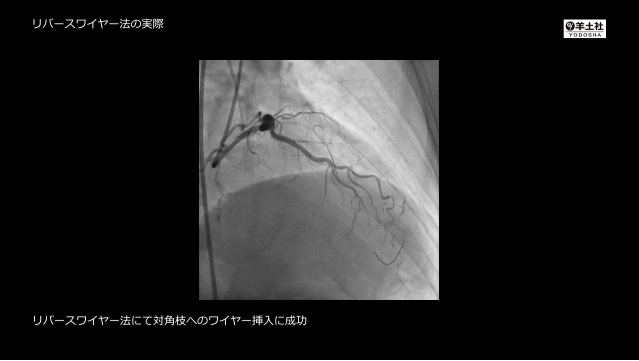

こうすれば必ず通過する!PCI医必携ガイドワイヤー“秘伝, 確実に身につくPCIの基本とコツ 第3版〜カラー写真と動画でわかるデバイスの選択・基本手技と施行困難例へのテクニック - 羊土社,

確実に身につくPCIの基本とコツ 第3版〜カラー写真と動画でわかるデバイスの選択・基本手技と施行困難例へのテクニック - 羊土社, 確実に身につくPCIの基本とコツ 第3版〜カラー写真と動画でわかるデバイスの選択・基本手技と施行困難例へのテクニック - 羊土社,

確実に身につくPCIの基本とコツ 第3版〜カラー写真と動画でわかるデバイスの選択・基本手技と施行困難例へのテクニック - 羊土社, Arm Cortex-M23/M33プロセッサ・システム開発ガイド / Yiu,Joseph【著】/五月女 哲夫【訳】 - 紀伊國屋書店ウェブストア|オンライン書店|本、雑誌の通販、電子書籍ストア